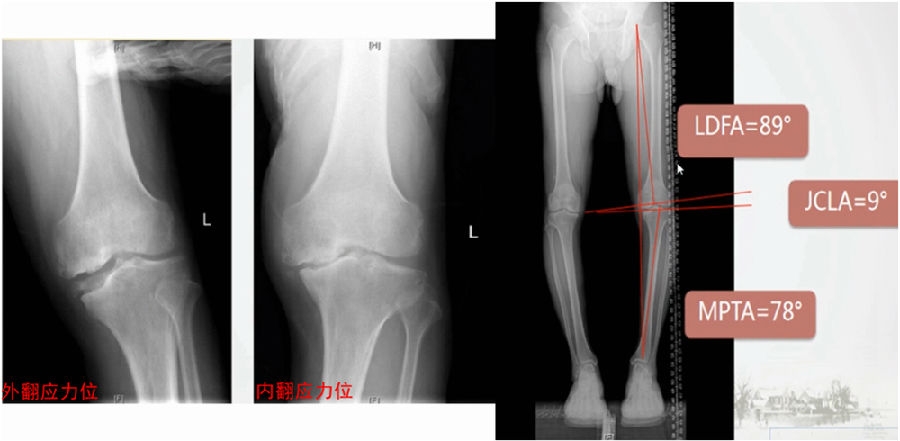

典型病例,男性,57岁,农民,左膝疼痛3年。

术前

术前影像资料

术前MRI

术前规划:

①关节内截骨,内外侧平台平行。

关节内截骨

②再次确定下肢力线。

确定力线

③关节外截骨。

关节外截骨

④术中首先关节镜探查。关节镜下软骨损伤3度,软骨脱落,软骨下骨暴露。

关节镜下所示

⑤同时做微骨折处理。

微骨折处理

术中先打克氏针确定截骨方向,先做关节内截骨,截完后测量下肢力线,发现并没达到术前设计的Fujisawa点。

术中影像资料

随后用骨刀继续向前敲,做HTO内侧开放楔,截骨完成后内侧固定,并测量下肢力线,此时达到术前设计的要求。

该患者撑开较大,取了髂骨进行植骨。

髂骨植骨

最终力线

术后检查证实达到了术前预期的手术效果,关节线达到了平行,半脱位得到矫正,同时关节线和地面水平。病人行走达到了理想的效果。

术后X线

患者术后4个月截骨愈合,膝关节稳定维持得非常好。

术后4个月

术后9个月完全恢复功能状态。

术后9个月